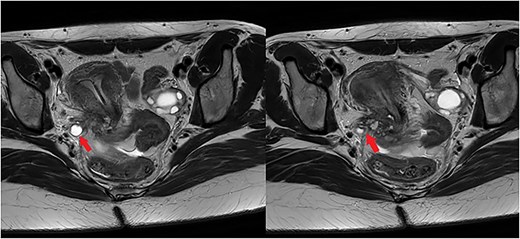

A 29-year-old G1P0A1 with a history of severe dysmenorrhea and chronic pelvic pain was referred to our tertiary center for surgery, after being diagnosed with DIE in the right parametrium and encasing the right ureter on ultrasonography. Further preoperative imaging with magnetic resonance imaging (MRI) revealed DIE on the posterior wall of the cervix with several T2 hypo-intense small cysts (with protein rich content), extending to the torus uterinus and to thickened right uterosacral ligament; the right ureter was dilated (hydroureter) and medially distorted by a T2-hypointense cordly-shaped zone in the right parametrium (Fig. 1). The endometriosis in the right antero-lateral parametrium was encasing the right distal ureter (Fig. 1); there was evidence of hydroureteronephrosis.

The left image illustrates a dilated right ureter (arrow) due to the presence of endometriosis in the right parametrium, as a T2-hypointense cordly-shaped zone in the parametrium. The right image shows endometriosis in the right antero-lateral parametrium encasing (arrow) the right distal ureter.